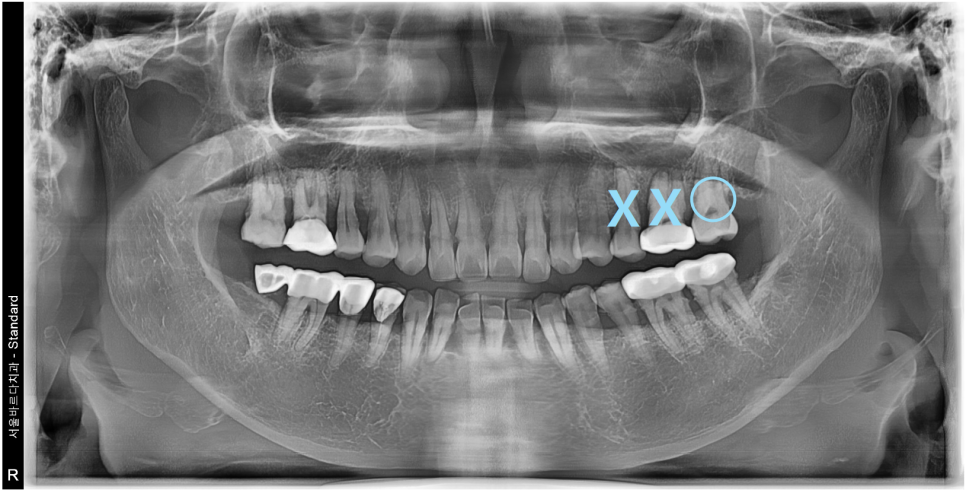

씹을때 먹먹하고 한쪽으로만 식사를 하신다는 이야기를 듣고

전반적으로 뼈와 치아 상태를 확인하는

파노라마 엑스레이를 촬영하여 보니

통증이 있다고 하는 왼쪽 위 큰어금니2개와

바로 그 앞의 작은어금니가 많이 흔들리는 상황이였습니다.

다수의 치아가 흔들리는 상황이였기에

치아의 뿌리를 조금 더 정밀하게 볼 수 있는

치근단 엑스레이와 CT를 추가적으로 촬영하였습니다.